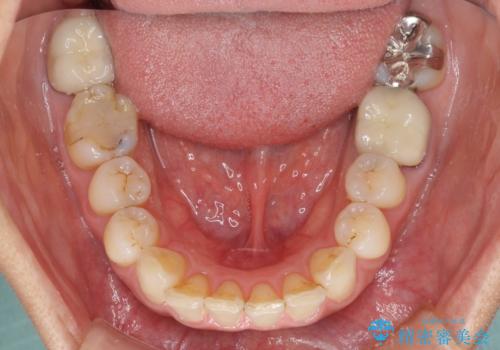

- 以前行った抜歯矯正が後戻りし、開いてしまったスペースが気になるとのことで来院された患者様です。

インビザラインを用いて開いてしまったスペースと前歯のデコボコを改善することとしました。

矯正治療後には気になっていた銀歯をセラミッククラウンやセラミックインレーにて治療することとしました。

上顎前歯を左右対称となるように歯列を整えたいとのことでしたが、すり減って形態が大きく異なっていたため、できる範囲での仕上がりとなりました。